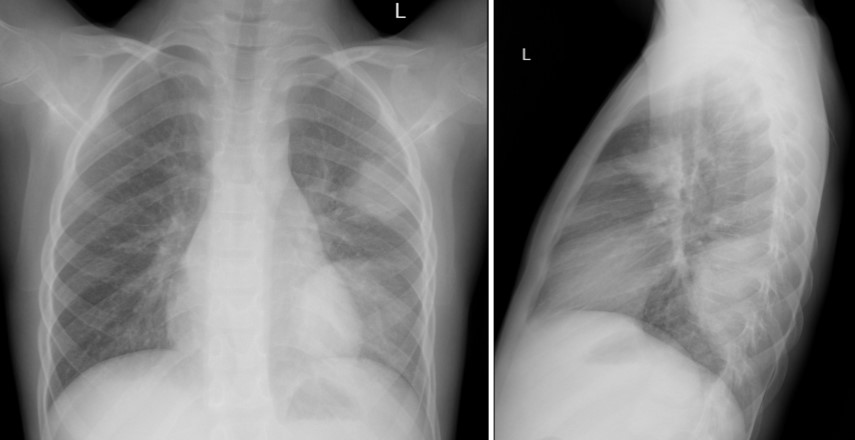

- рентгенография органов грудной клетки от 15.12.2024: слева в проекции периферических отделов S3 и S9-10 определяются два крупных участка затемнения с несколько нечеткими контурами, однородные по структуре. В остальных отделах легочные поля прозрачные, без очагов и инфильтративных изменений (рис.1)

Рисунок 1 - На рентгенограмме органов грудной клетки определяются полисегментарные инфильтративные изменения в левом легком